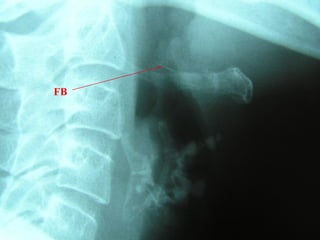

FB Throat - Investigations

Lateral neck XR

CXR

Barium swallow

CT scan – without contrast

Rigid oesophagoscopy

FB

Hyoid bone

Thyroid cartilage

Cricoid cartilage

Osteophyte